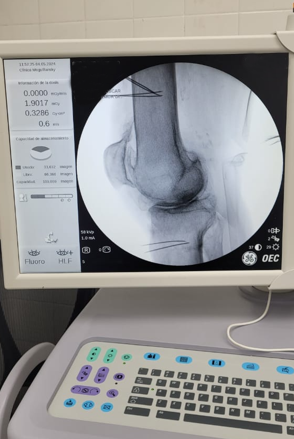

Paciente con dolor intenso por artrosis severa de rodilla

Candidato a un reemplazo total de rodilla, el paciente sentía un dolor tan intenso que le impedía la marcha.

Por la morbimortalidad de la cirugía, se procede a realizar en Tidol un tratamiento con radiofrecuencia, debido al dolor intenso que le impedía la marcha.